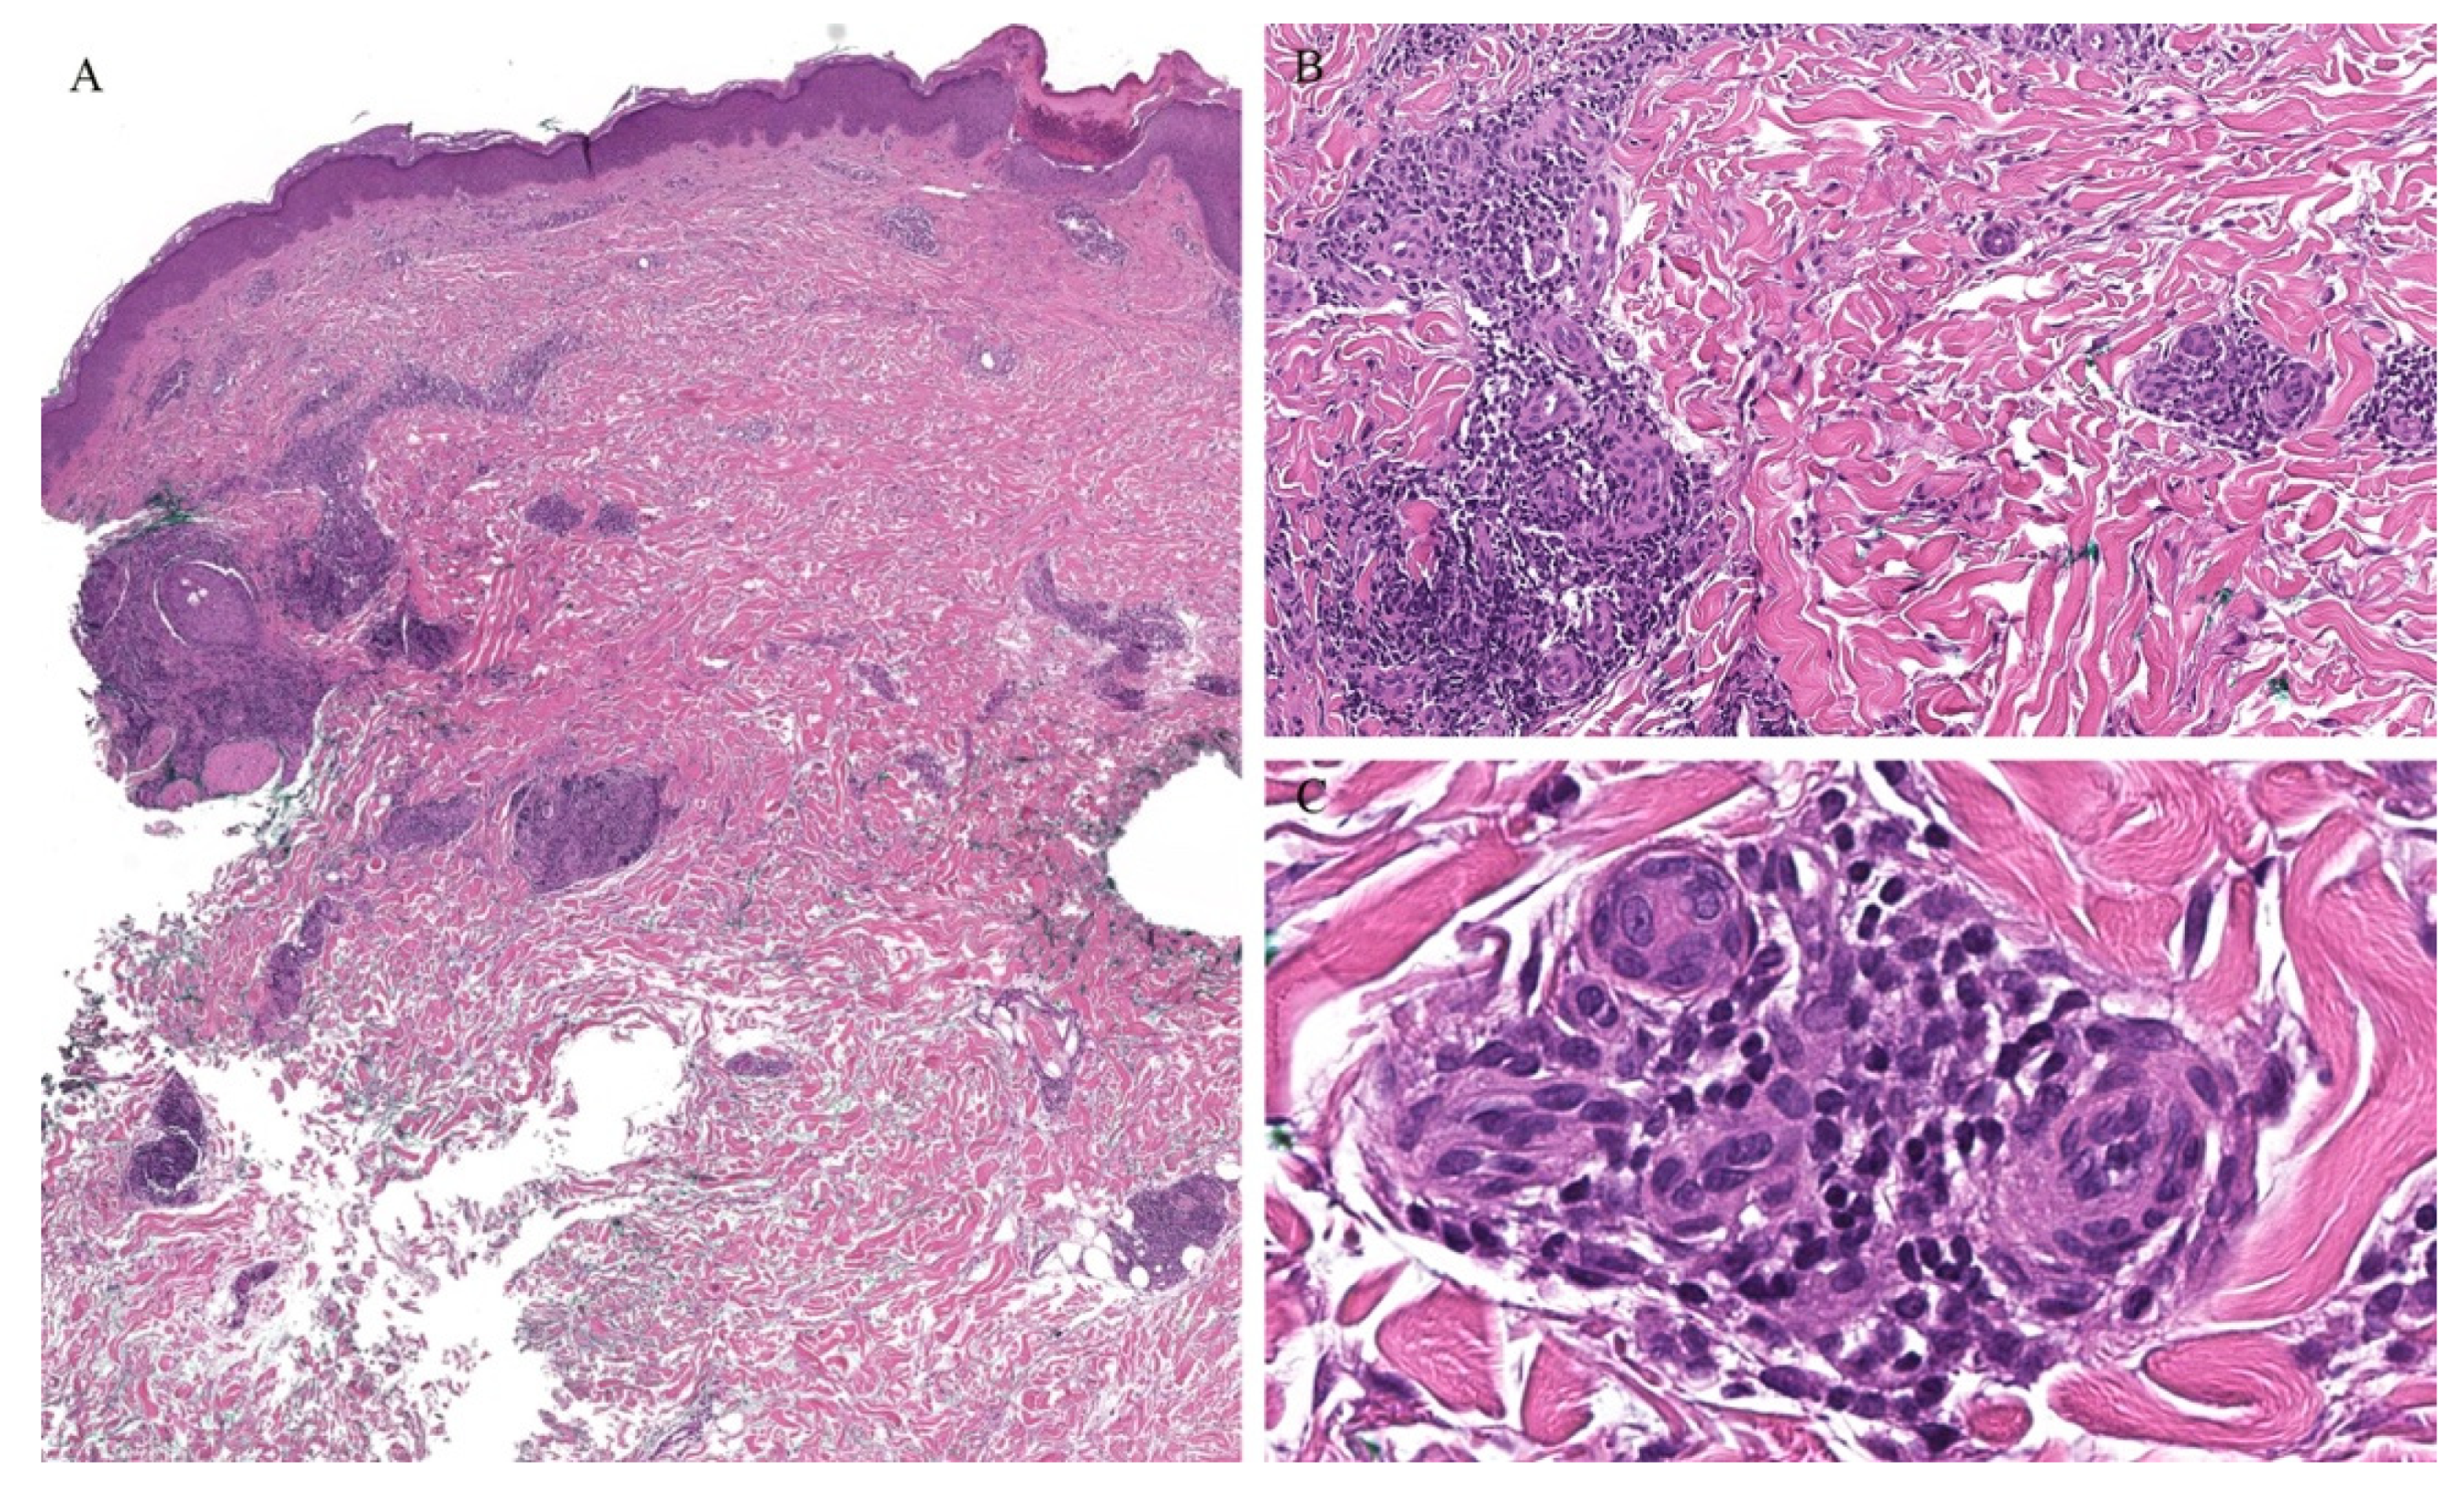

Clinically, the involvement of the hair follicle in GVHD can result in a variety of manifestations including non-scarring and scarring alopecias, a follicular rash, and comedonal lesions, among others [11]. Histologically, follicular variants have been described in both acute and chronic forms of GVHD (Figure 2) [12]. Unfortunately, the reported cases of acute follicular GVHD carried a high mortality rate while chronic follicular GVHD seems to confer a more favorable prognosis [13,14]. This involvement of the follicular epithelium has been attributed to inflammation around the bulge region of the hair follicle, likely due to the presence of stem cells in this area [15].

Eccrine gland involvement is also seen in GVHD. In addition to the classical histologic features, a lymphoplasmacytic infiltrate around the eccrine coils is a specific feature of GVHD (Figure 2) [16]. Eccrine squamous syringometaplasia has also been described in biopsy specimens of a patient with cutaneous and hepatic GVHD [17].

Figure 2. (AC) Graft versus host disease with perieccrine inflammation.